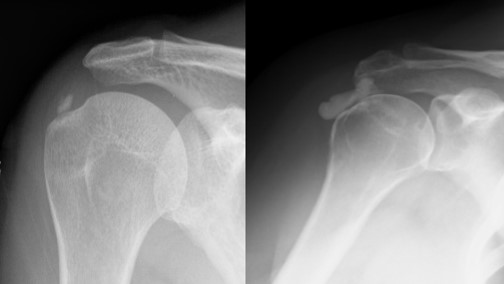

진단/검사

석회성건염의 진단은 환자의 증상 및 병력(주로 중년 이후의 환자에서 외상없이 갑자기 발생한 극심한 통증)으로 의심을 할 수 있으며, X-ray 검사로 간단히 진단을 할 수 있다. 하지만, 동반된 다른 질병을 감별하기 위해서, 혹은 보존적 치료에 반응하지 않아 수술적 치료를 시행하기 위해서 MRI 등 추가 검사를 시행해 볼 수 있다.